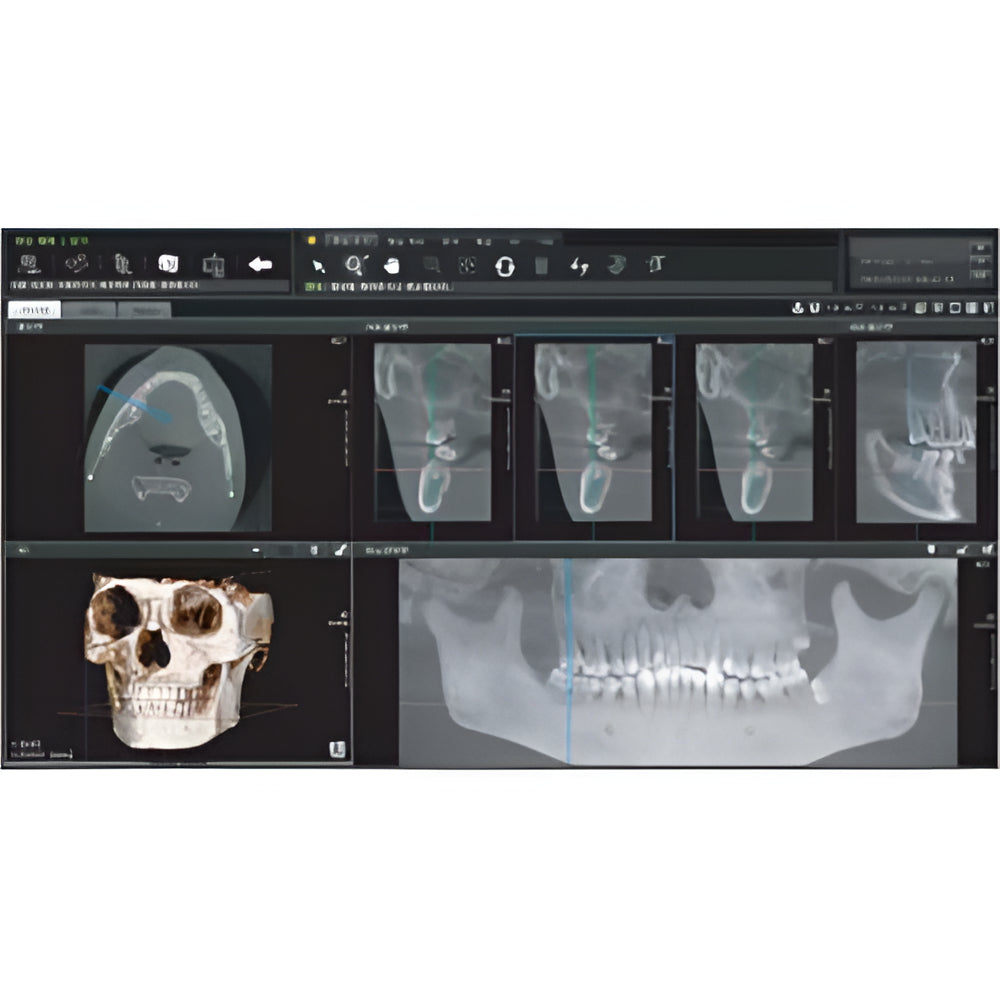

Papaya uses the CdTe sensor, which improves image quality while keeping radiation exposure to a minimum. The CdTe (Cadimium telluride) sensor overcomes the limitations of a CMOS sensor to always produce high quality images.

- 3D imaging software

- Field Of View: 4x5, 7x7, 8x8, 14x8, 14x14

- Multi-FOV selection

- 7.7 sec fast scan for 3D image

- Large FOV